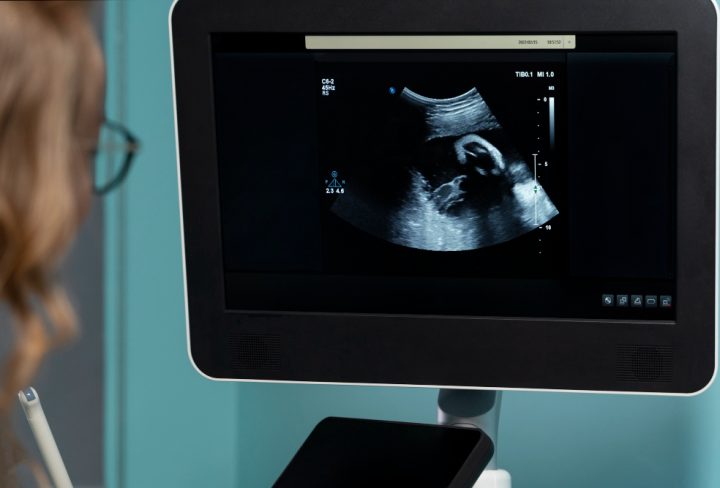

A placental localization scan is a special type of pregnancy ultrasound. It shows the exact spot where the placenta attaches inside the uterus. Usually, this scan is done during a regular pregnancy ultrasound scan. However, sometimes doctors order it if they need more details. The scan uses sound waves to create pictures of the placenta and baby. It does not use any harmful radiation. Because of this, it is safe for both mother and baby. The main goal is to check if the placenta is in a safe spot for delivery.

First, you will be asked to lie down on an exam table. Next, a gel is spread on your belly. This gel helps the ultrasound device move smoothly and send clear images. Then, the technician moves a small device called a transducer over your skin. The device sends sound waves into your body. These waves bounce back and create pictures on a screen. Sometimes, if the placenta is low or hard to see, a vaginal ultrasound may be needed. This is safe and usually not painful. The whole scan takes about 15 to 30 minutes. After the scan, you can return to your normal activities right away.